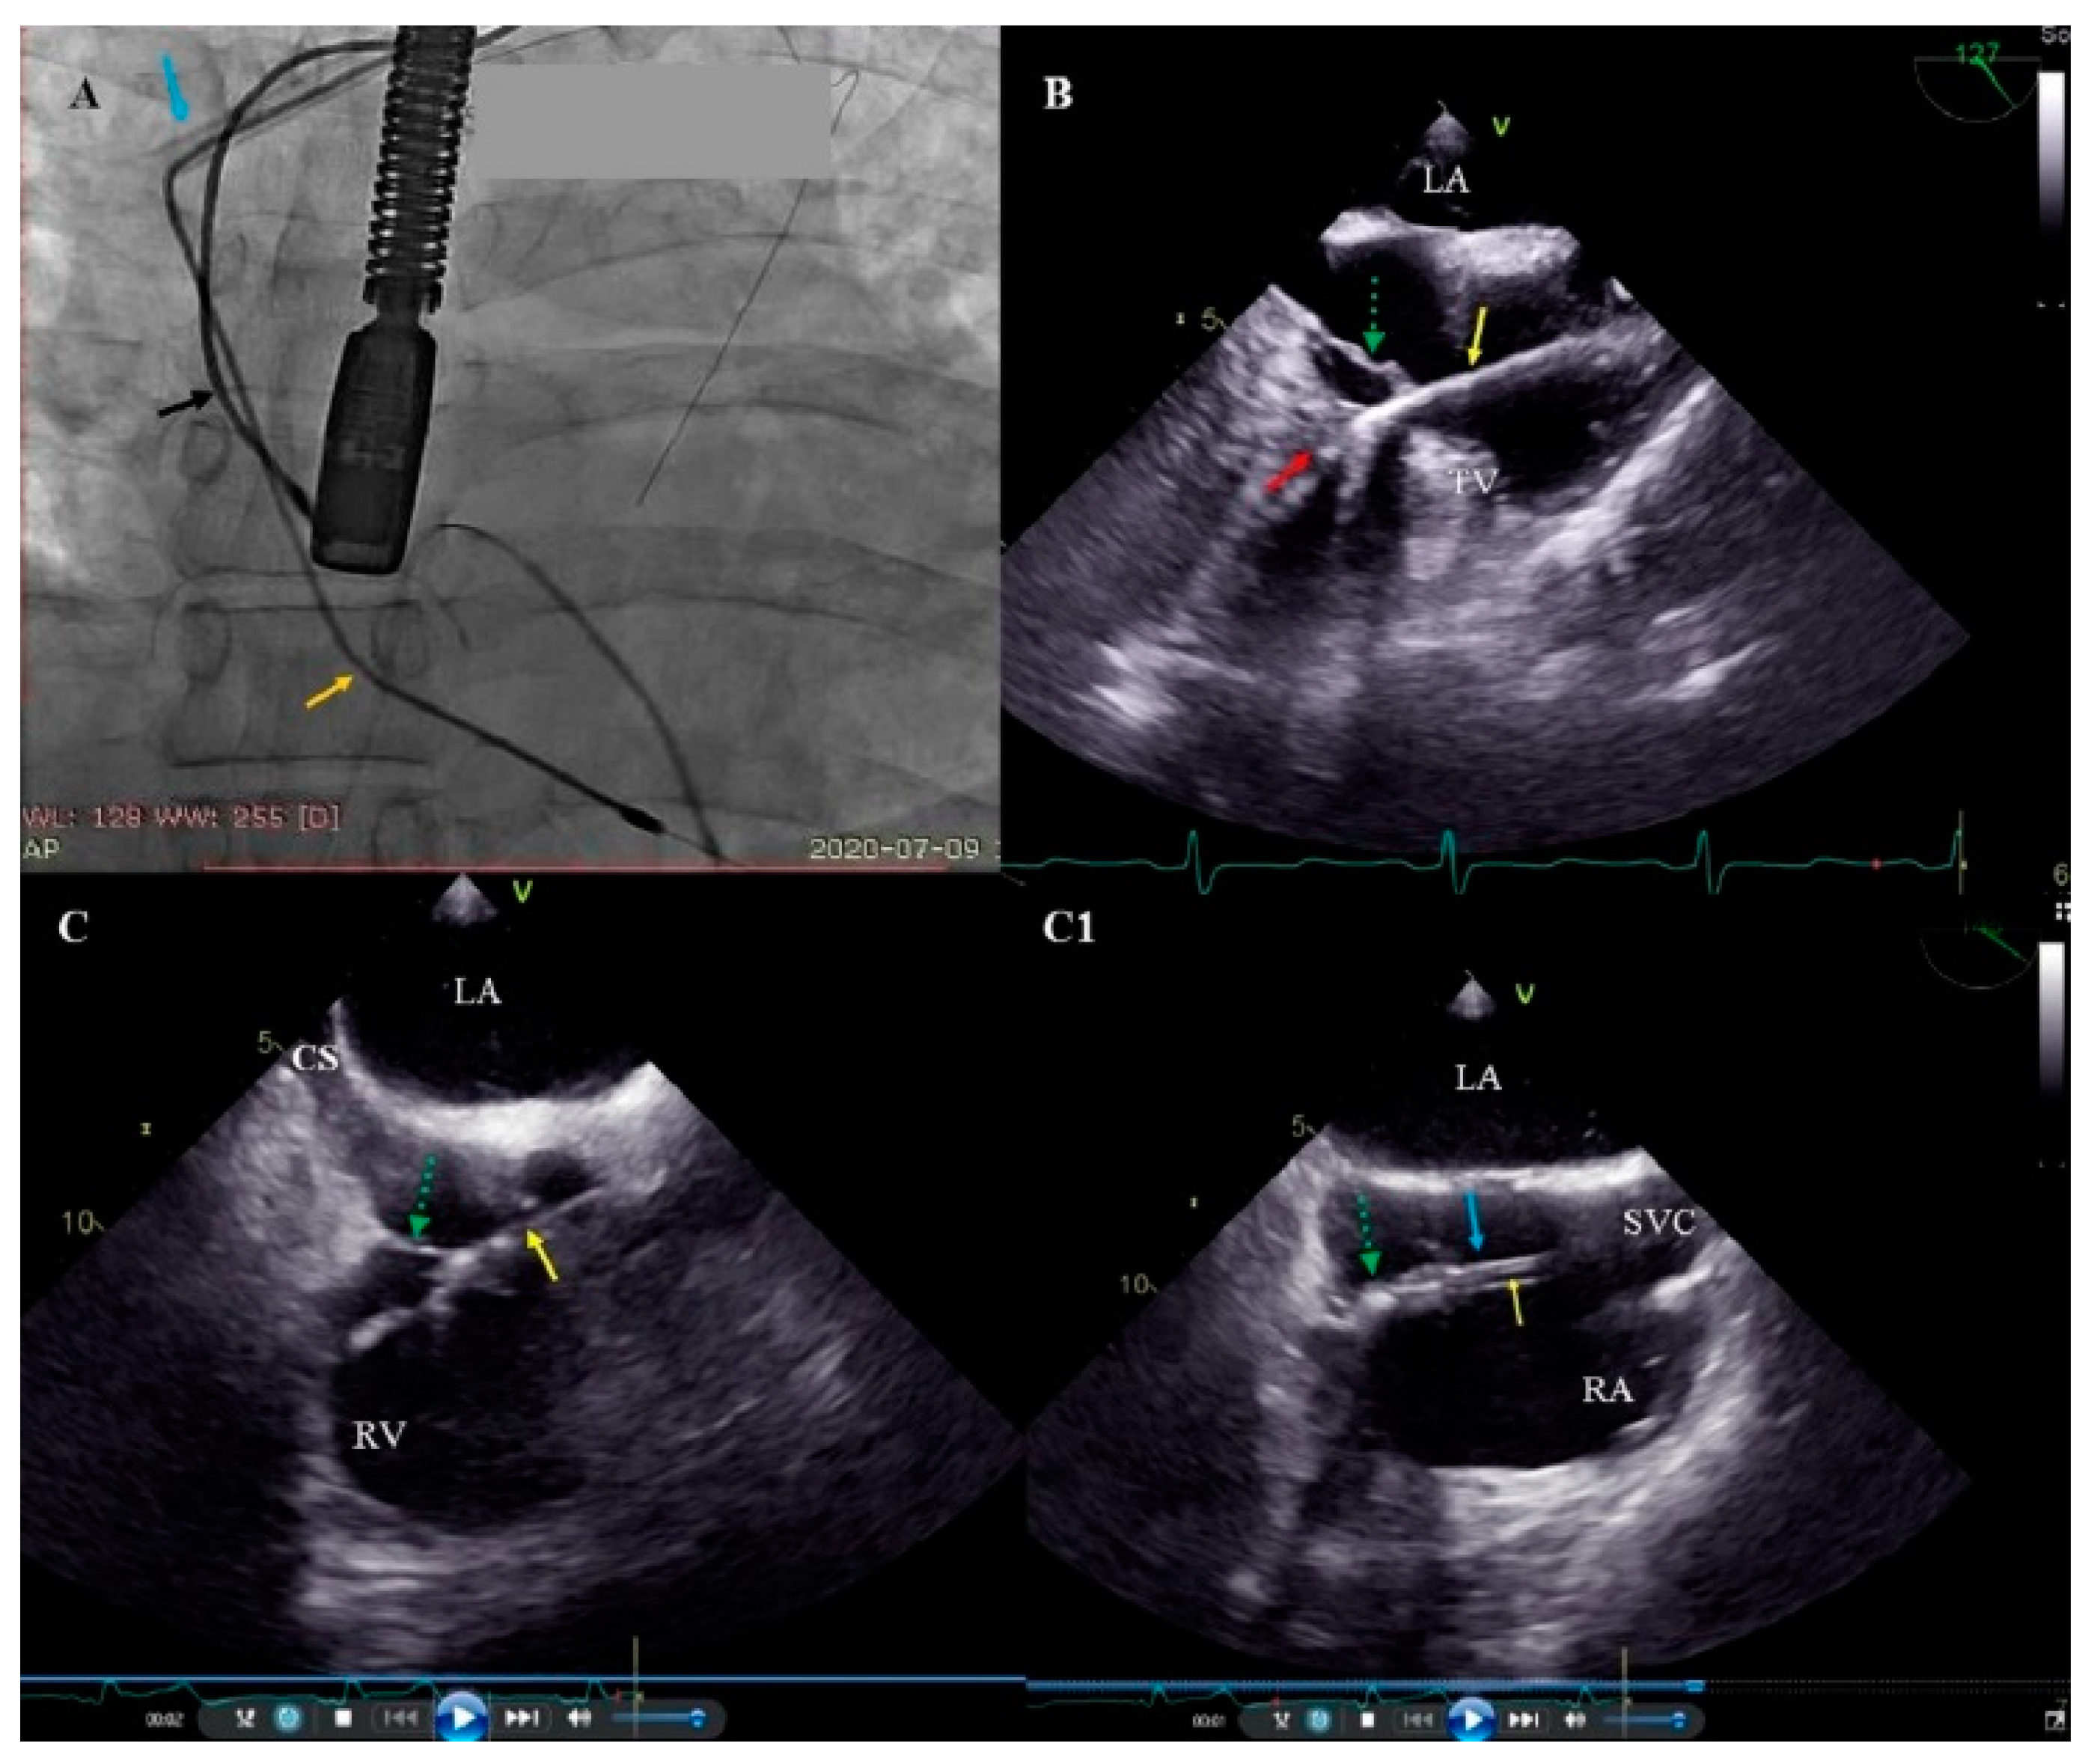

2.5. Echocardiographic Examinations

2.6. Tricuspid Valve Damage Evaluation

- Nowosielecka, D.; Jacheć, W.; Polewczyk, A.; Tułecki, Ł.; Tomków, K.; Stefańczyk, P.; Tomaszewski, A.; Brzozowski, W.; Szcześniak-Stańczyk, D.; Kleinrok, A.; et al. Transesophageal Echocardiography as a Monitoring Tool during Transvenous Lead Extraction—Does It Improve Procedure Effectiveness? J. Clin. Med. 2020, 9, 1382. [Google Scholar] [CrossRef]

- Nowosielecka, D.; Polewczyk, A.; Jacheć, W.; Tułecki, Ł.; Tomków, K.; Stefańczyk, P.; Kleinrok, A.; Kutarski, A. A new approach to the continuous monitoring of transvenous lead extraction using transesophageal echocardiography—Analysis of 936 procedures. Echocardiography 2020, 37, 601–611. [Google Scholar] [CrossRef]

- Nowosielecka, D.; Polewczyk, A.; Jacheć, W.; Kleinrok, A.; Tułecki, Ł.; Kutarski, A. Transesophageal echocardiography for the monitoring of transvenous lead extraction. Kardiol. Pol. 2020, 78, 1206–1214. [Google Scholar] [CrossRef]

- Nowosielecka, D.; Jacheć, W.; Polewczyk, A.; Kleinrok, A.; Tułecki, Ł.; Kutarski, A. The prognostic value of transesophageal echocardiography after transvenous lead extraction: Landscape after battle. Cardiovasc. Diagn. Ther. 2021, 11, 394–410. [Google Scholar] [CrossRef]